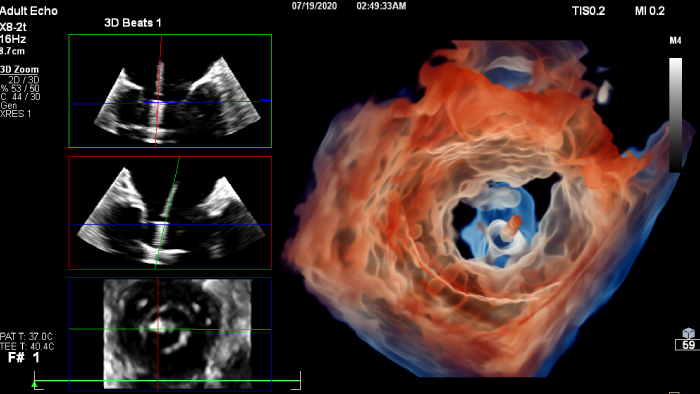

Cardiovascular Ultrasound

Increase diagnosis confidence and clinical efficiency through superior image quality, advanced quantification tool and automation technology.